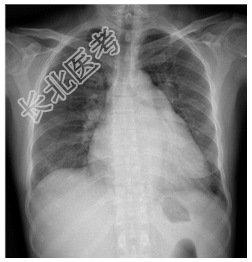

- [材料题] 患者,女性,48岁,劳累后心悸、气促2年余,加重伴呼吸困难1周。查体:患者颧部潮红,心尖区可闻及舒张期隆隆样杂音,第二心音亢进、分裂,双肺可闻及细湿啰音。心界向两侧扩大。行胸部平片检查。

- 简答题1、诊断及依据是什么?

- 简答题2、鉴别诊断有哪些?